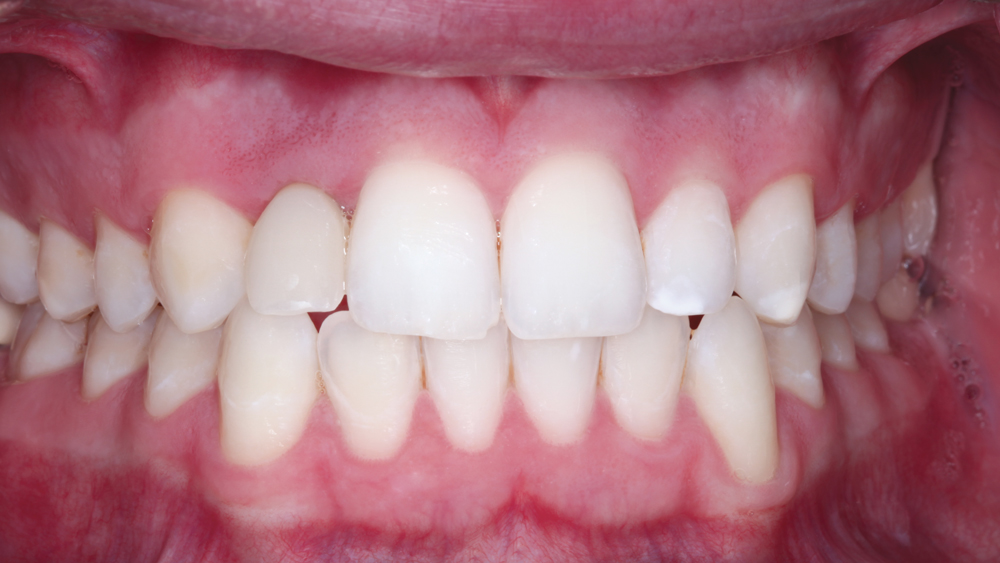

The following case illustrates the efficient, straightforward clinical workflow for placing Hahn Tapered Implants via guided surgery. A digital treatment plan is developed in which a 3.5 mm implant is positioned to support the ideal prosthetic outcome. An immediate provisional crown is designed in concert with the surgical guide and delivered at the time of surgery, helping to produce a predictable, highly esthetic restoration for a demanding case in the smile zone.